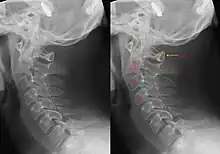

| Hangman's fracture | Hangman | fracture of both pedicles of C2 | distraction and extension of neck | Hangman's fracture Archived 2020-09-18 at the Wayback Machine at Wheeless' Textbook of Orthopaedics online |